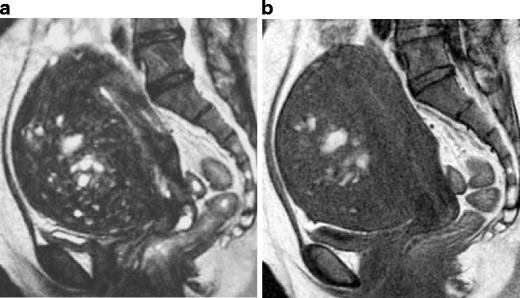

Red degeneration in a 36-year-old woman. a Sagittal T2-weighted image demonstrates a well-defined myometrial mass of low intensity, associated with thick rim of distinct low signal intensity (arrows). b T1-weighted image reveals entirely increased intensity in the tumor, suggesting red degeneration